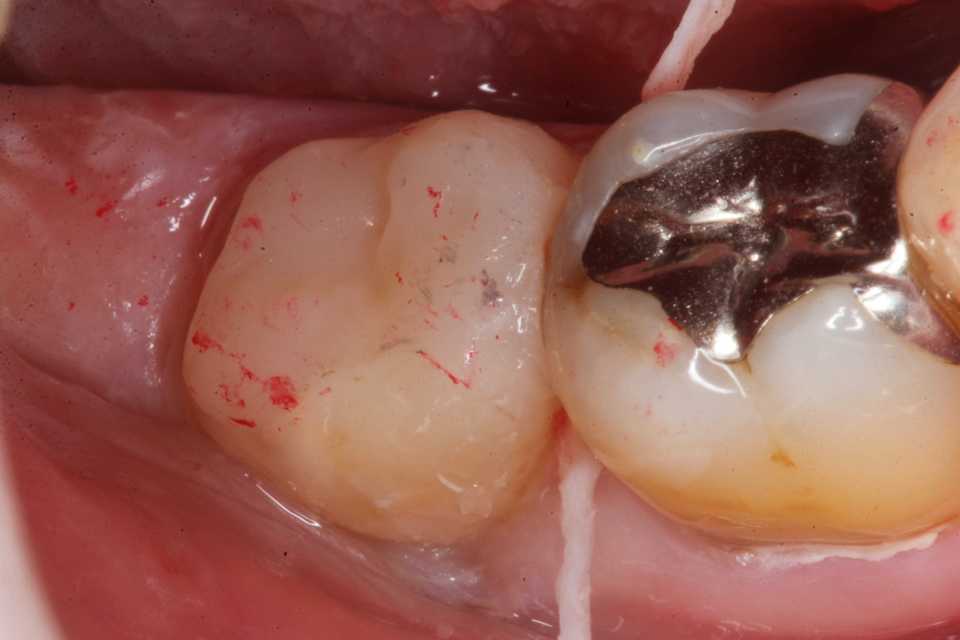

ストリップスを使わない隣接面CR(ダイレ… 2025.11.26

ストリップスを使わない隣接面CR(ダイレ… 2025.11.07